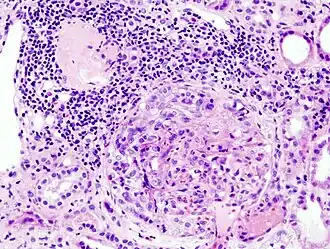

| Histopatologia de glomerulonefrite com formação Crescente causada por anticorpos antineutrófilos citoplasmáticos (ANCA). | |

Após identificar o rápido compromisso da função renal com um exame de creatinina, ureia, albumina e hemácias no sangue e na urina é recomendado uma ultrassonografia dos rins para ver se os rins estão aumentados, biópsia renal para ver se há padrão de "lua crescente" nos glomérulos (visível em até 75% dos casos) e um exame de autoanticorpos (ANA, ANCA e Anti-GBM).[3]